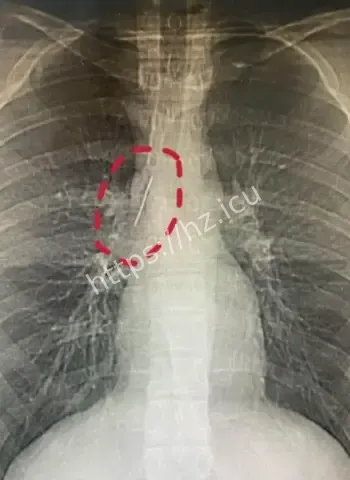

参军体检本来是查身体合不合格,谁知道成了挖宝现场。X光一扫,医生估计当时就傻眼了,这么大一根针亮闪闪地躺在胸腔里,小伙子自己都蒙圈了,心想我这身体里藏了啥秘密武器啊。幸好发现及时,要不然以后训练强度一大,万一针跑偏了,后果真不敢想。 这事儿也给大伙提了个醒,重要关口体检千万别马虎,尤其是参军这种人生大事,啥隐藏问题都能揪出来。小伙子估计现在又惊又喜,喜的是没出大事,惊的是自己居然带了17年“隐形伴侣”。

深入扒一扒,这针为啥能跟身体和平共处这么久呢。首先位置挑得好,没扎着要害器官,胸腔空间大给它留了余地。其次人体有自我保护本能,会分泌纤维组织慢慢把它包裹住,防止感染和移位。小时候扎入,身体还在发育,适应起来更容易。再次可能没带细菌进去,运气成分占大头。 这案例搁医学上都算罕见,值得研究研究,说不定以后处理类似异物就有新办法了。不过小伙子以后肯定得做个小手术取出来,不然总是个小隐患。希望手术顺顺利利,他的参军梦还能接着追,这段经历以后说出去绝对是别人听不够的传奇。